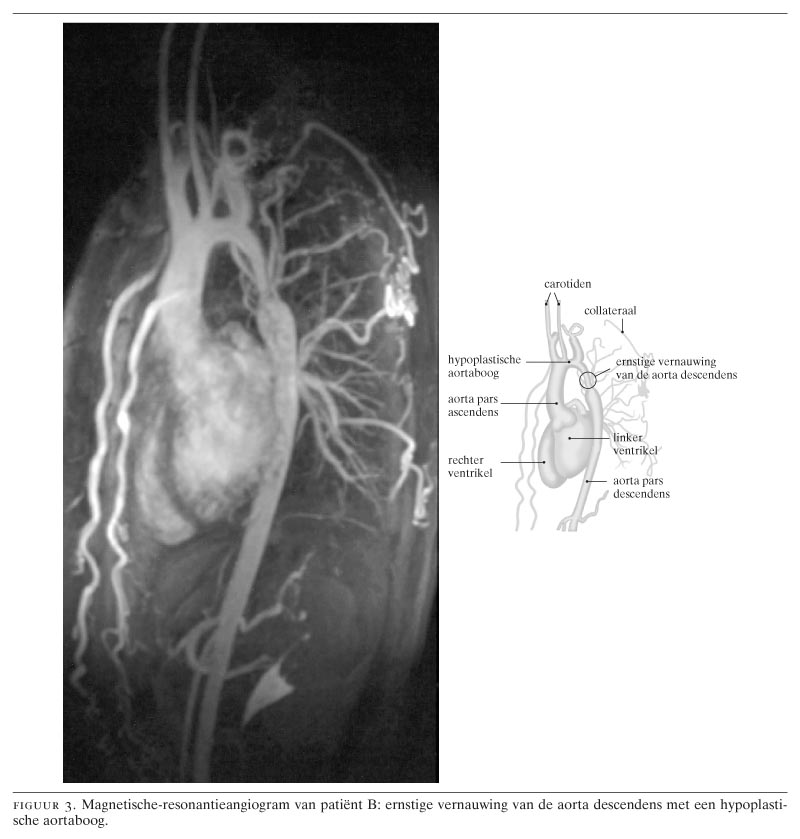

Collega's Vriend et al. (2004:161-6) wijzen op de mogelijkheid van een coarctatio aortae als een zeker niet zeldzame, te corrigeren oorzaak van hypertensie bij jongvolwassenen. Als die mogelijkheid ook wordt overwogen, is de diagnose eenvoudig te stellen, soms zelfs al bij lichamelijk onderzoek. Tijdige behandeling kan vaak de gevolgen van langdurige hypertensie voorkomen, evenals de noodzaak tot levenslange antihypertensiemedicatie. Als enige therapeutische behandelingsoptie van de coarctatio aortae vermelden de auteurs chirurgische resectie. Sinds deze ingreep voor het eerst in 1945 door Crafoord en Nylin beschreven werd,1 is die algemeen aanvaard en wordt die met goed resultaat toegepast. De auteurs laten na een alternatieve behandelingswijze voor een coarctatio aortae te vermelden, namelijk de percutane benadering door middel van een ballondilatatie (percutane transluminale angioplastiek; PTA). Wij zouden hierop willen wijzen als therapeutische optie bij de klassieke segmentale coarctatio (zoals bij patiënt A en C); alleen bij bijkomende aandoeningen als hypoplasie van de aortaboog of van de aorta descendens (zoals bij patiënt B) is een chirurgische benadering geïndiceerd.